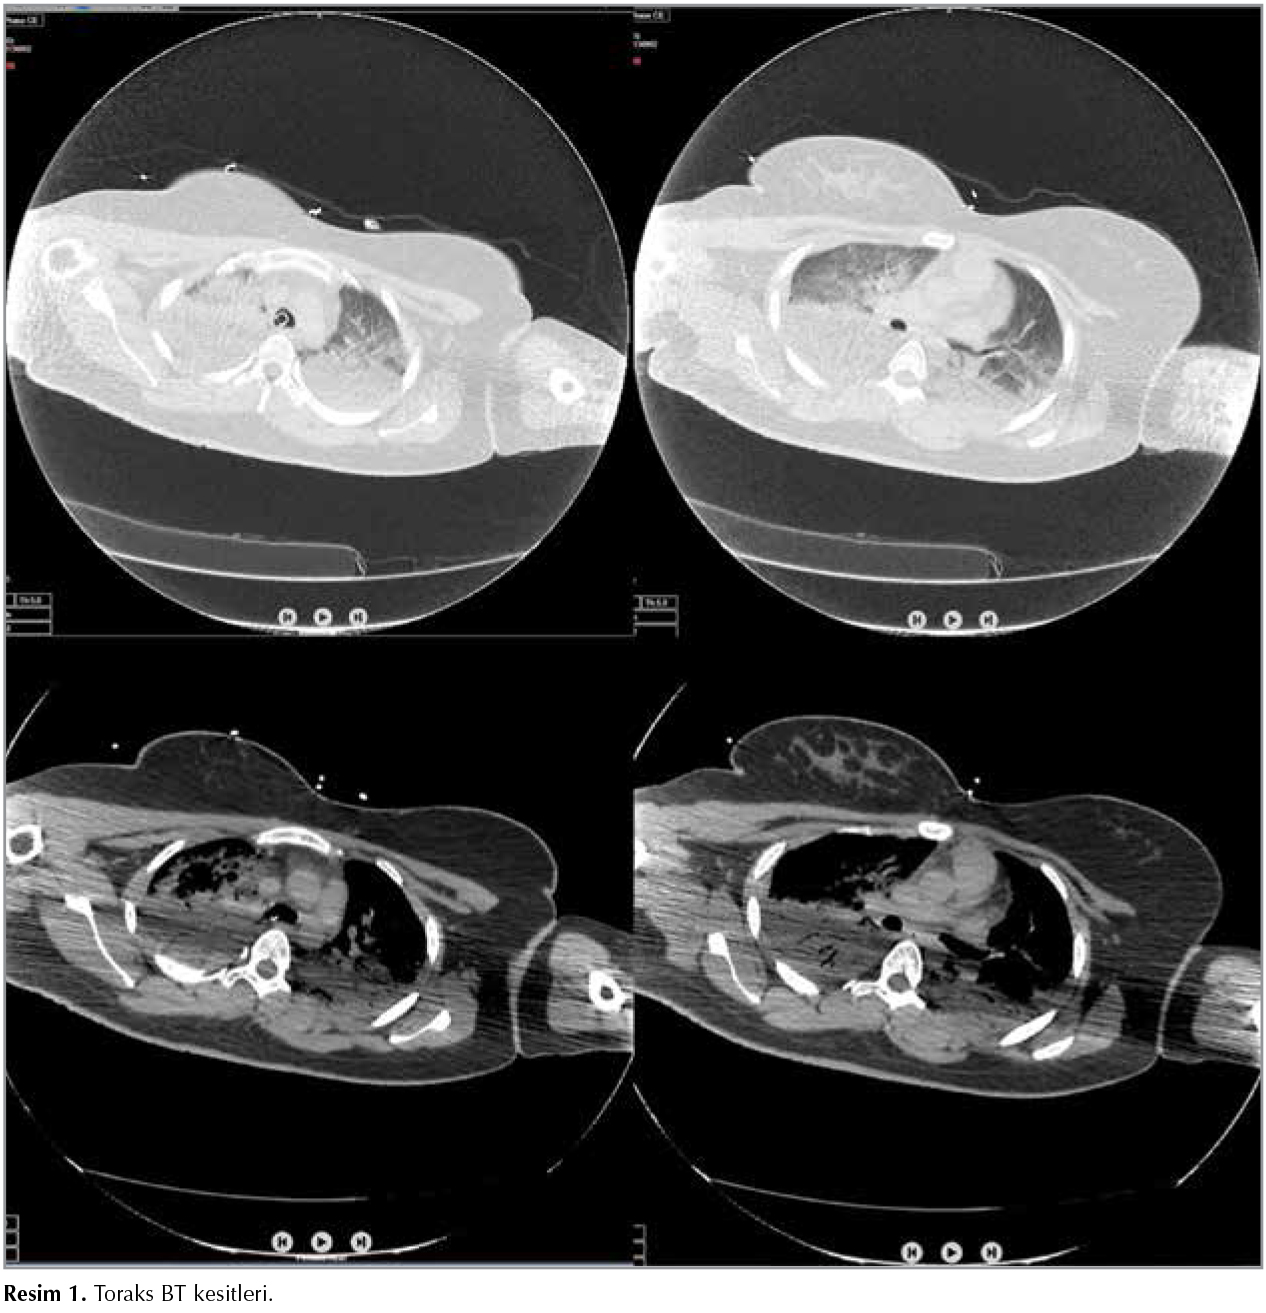

Yirmi altı yaşında kadın hasta, t?pl? şofbenle su ısıtılan (%70 b?tan ve %30 propan karışımı) banyoda 20 dakika ge?irdikten sonra baygın vaziyette bulunmuştur.? Ent?be halde, GKS: 3, pupiller fiks dilateyken ilk bakılan karboksihemoglobin (COHb) %67, kontrol? %33.9 olarak değerlendirilmiştir. Hastanın acil servisimizde bakılan en k?t? kan gazında pH: 7.19, pCO2: 43.5 mmHg, pO2: 490 mmHg, HCO3: 15.4 mEq/L, BE: -11 ve COHb: %27.1 (N: 0.5 2.5) saptanmıştır. K?t? hemodinami, derin koma ve ağır ARDS tablosu nedeniyle (il i?erisinde hiperbarik oksijen tedavisi imkanı yoktur) hastanın hiperbarik oksijen i?in sevki planlanamamıştır. Hasta takibi i?in yoğun bakım ?nitemize devralınmıştır. Genel durumu k?t?, şuuru koma, GKS: 3 olan hastanın santal sinir sistemi değerlendirilmesi i?in ?ekilen BBT'sinde ventrik?ler sistem silinmiş, beyaz-gri cevher ayrımı kaybolmuş ve fiss?rler silinmiş olarak izlenmektedir. ?ekilen Torax BT'sinde her iki akciğer bazal ve posteriorlarda hava bronkogramları g?steren konsolide alanlar ve diğer alanlarda yaygın buzlu cam dansiteleri izlendi (Resim 1). Servisimize ilk kabul?ndeki biyokimyasal değerleri Na: 167 mEq/L, K: 2.7 mEq/L, glukoz: 161 mg/dL, kreatin 0.96 mg/dL, BUN: 9.7 mg/dL, hemoglobin: 8 g/dL, COHb: %20.9, ?l??lm?şt?r. Hipotansif seyreden hastaya (OKB < 65 mmHg) hemodinamik instabilite nedeniyle dopamin inf?zyonu (1 μg/kg/dk) başlanmıştır. Ciddi beyin ?demi nedeniyle mannitol 6x100 mg IV başlandı. Mekanik ventilat?rde airway pressure releasing ventilation (APRV) modda (FiO2: %100, Phigh: 20 cmH20, Plow: 0 cmH20, Thigh: 4 sn, Tlow: 0.8 sn) takip edilen hastada 2 saat sonra oksijenizasyonda belirgin iyileşme, kan gazında d?zelme, COHb'de normalizasyon (COHb: %0.3) ve kontrol APAC grafisinde belirgin d?zelme sağlanmıştır (Resim 2). Bilin? durumunda d?zelme olmayan hastada apne testi, n?rolojik muayene ve BT anjiyoyla beyinde kan akımı olmadığı ve beyin ?l?m? tanısı doğrulanmıştır. Hasta yatışının 2. g?n?nde yakınlarının da onamıyla b?brek ve karaciğer don?r? olmuştur.

Resim 1